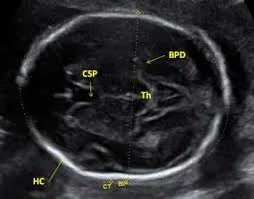

Dead Fetus

- Absence of flow and heart movements

- Oligohydramnios

- Superposition of skull bones

Spalding sign